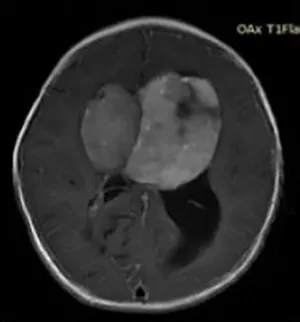

一岁小朋友巨大视神经胶质瘤,三名国际教授连夜提供第二意见

INC三位海外儿童神外专家在看过小晴的情况后,得出了总体上比较一致的咨询建议——患儿很可能为鞍区视神经胶质瘤,这通常是低级别或良性肿瘤,且治愈率较高。这种低级别胶质瘤治疗方法是完全彻底地手术切除,这对于解除大脑的局部压力非常重要,但同样也要面临手术所承担的风险,包括垂体功能不全、视力障碍和中风等。如果能够最大程度安全切除,则预后生存率会非常好,不会干扰正常的生活,后续持续跟踪及接受适当的治疗,则可与一般人寿命相似,但对于复发率的评估需要根据肿瘤的级别及性质决定。

对于手术切除程度,INC三位海外儿科专家都有着比较明确的评估,一般都能达到80%以上的切除率,在这方面巴特朗菲教授在他的一系列临床病例中证明了⼤量全切/次全切除的可能性与良好的功能结果有关。手术过程中的风险与肿瘤的⾎管特征有关,因为婴⼉年龄很⼩,血液储备有限,这需要仔细的⿇醉处理、极为熟练的手术团队配合,也需要术中磁共振成像系统(iMRI)、术中神经电生理监测、术中神经导航等设备护航。